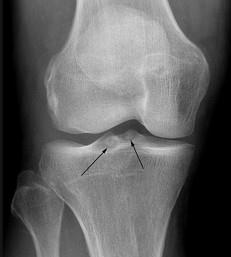

问题 女,65岁,右膝痛,活动受限,请结合图像,选出最可能的诊断 ( )

选项 A、类风湿关节炎 B、痛风 C、创伤性关节炎 D、退行性骨关节病 E、神经性关节病

答案 D